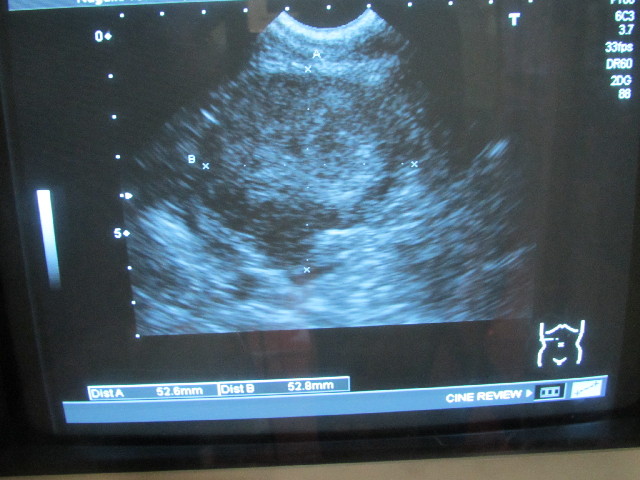

今日はべべちゃん腎臓の移行上皮癌(バブちゃん)の大きさを調べるエコー検査の日でした。

最大直径は2週間前と同じ約53ミリ(52.6×52.8mm)(^-^)v

発見当初は大きくなるのが速かったけど、ここ1〜2ケ月がグッと大きくなるペースが落ちました(^-^)v

2月27日からは約1mmしか大きくなっていないということ!